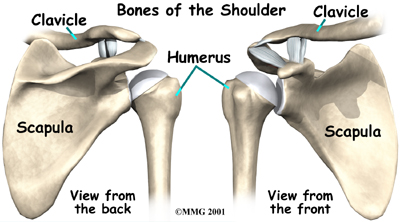

The shoulder is made up of : the scapula (shoulder blade), the humerus (upper arm bone,) and the clavicle (collarbone).

Tendons attach muscles to bones. Muscles move bones by pulling on tendons. The muscles of the rotator cuff also keep the humerus tightly in the socket. A part of the scapula, called the glenoid, makes up the socket of the shoulder. The glenoid is very shallow and flat. A rim of soft tissue, called the labrum, surrounds the edge of the glenoid, making the socket more like a cup. The labrum turns the flat surface of the glenoid into a deeper socket that molds to fit the head of the humerus.

Surrounding the shoulder joint is a watertight sac called the joint capsule. The joint capsule holds fluids that lubricate the joint. The walls of the joint capsule are made up of ligaments. Ligaments are soft connective tissues that attach bones to bones. The joint capsule has a considerable amount of slack, loose tissue, so that the shoulder is unrestricted as it moves through its large range of motion. If the shoulder moves too far, the ligaments become tight and stop any further motion, sort of like a dog coming to the end of its leash.